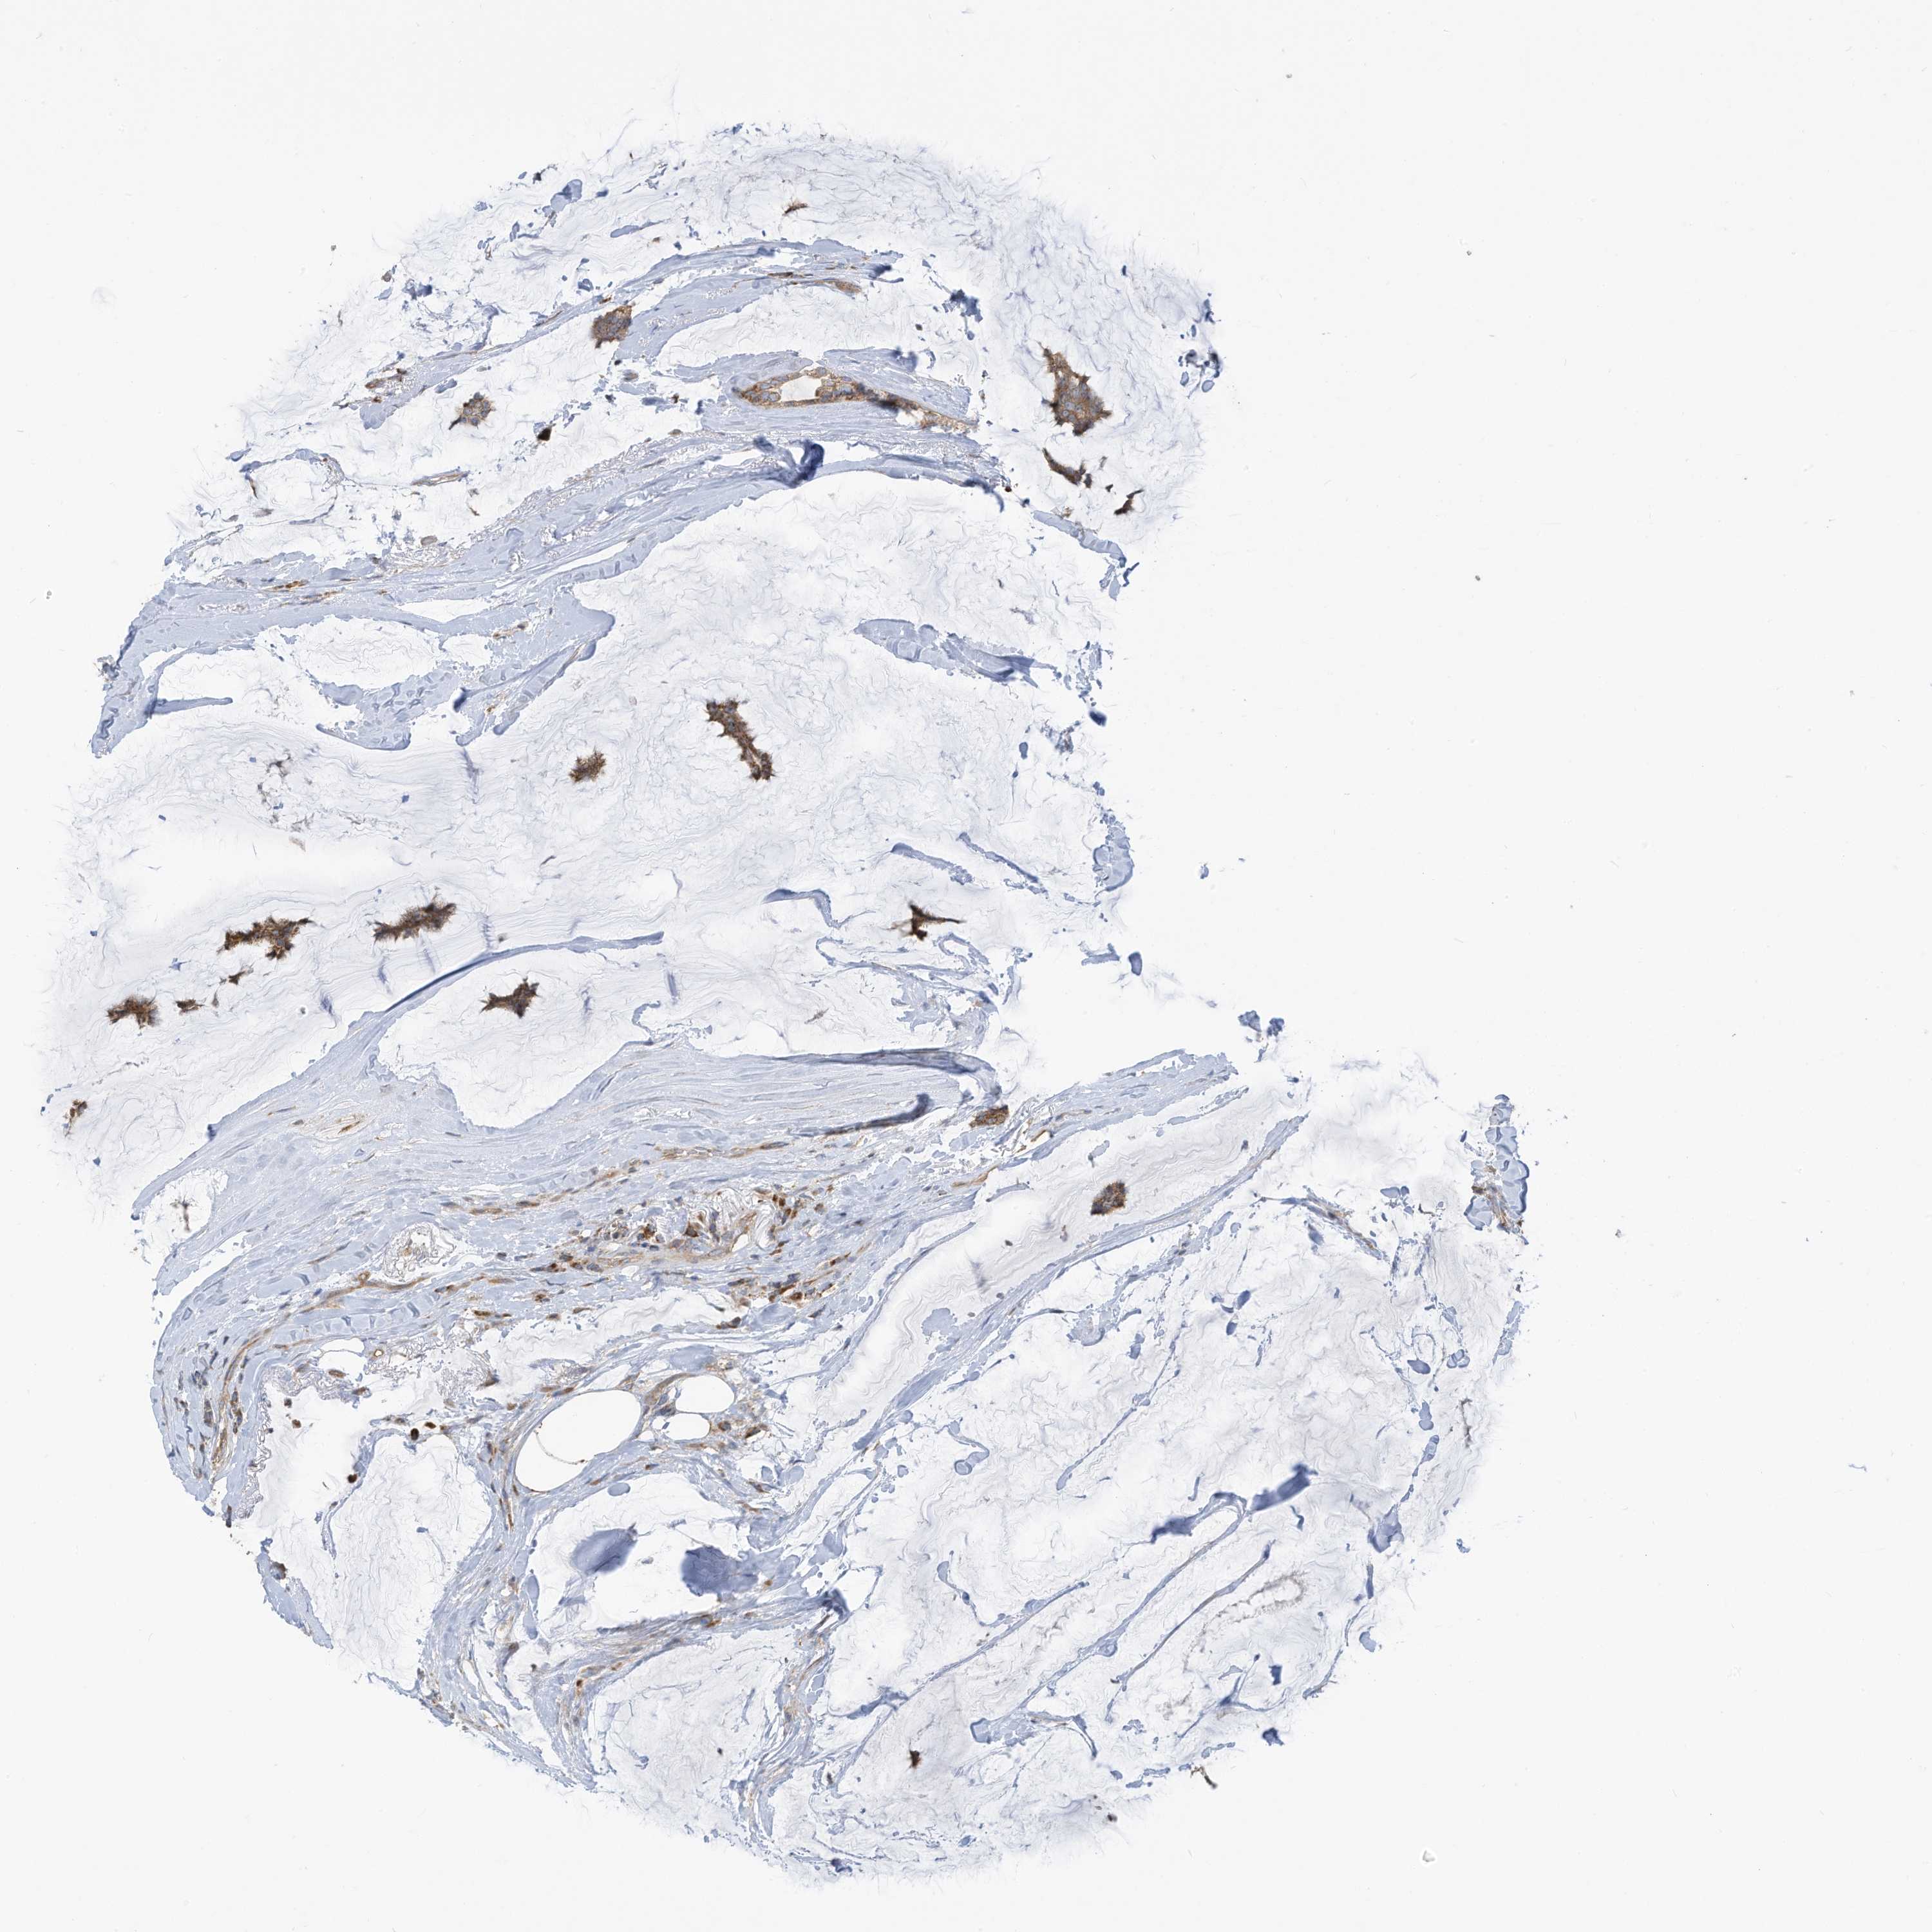

CANCER BREAST CANCER Show tissue menu

BRCA TCGA BRCA VALIDATION PROTEIN EXPRESSION